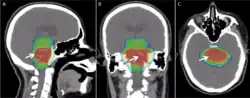

Modern radiation therapy relies on a CT scan to identify the tumor and surrounding normal structures and to perform dose calculations for the creation of a complex radiation treatment plan. The patient receives small skin marks to guide the placement of treatment fields.[10] Patient positioning is crucial at this stage as the patient will have to be placed in an identical position during each treatment. Many patient positioning devices have been developed for this purpose, including masks and cushions which can be molded to the patient. Image-guided radiation therapy is a method that uses imaging to correct for positional errors of each treatment session.

Delivery parameters of a prescribed dose are determined during treatment planning (part of dosimetry). Treatment planning is generally performed on dedicated computers using specialized treatment planning software. Depending on the radiation delivery method, several angles or sources may be used to sum to the total necessary dose. The planner will try to design a plan that delivers a uniform prescription dose to the tumor and minimizes dose to surrounding healthy tissues.

The planning of radiation therapy treatment has been revolutionized by the ability to delineate tumors and adjacent normal structures in three dimensions using specialized CT and/or MRI scanners and planning software.[81]

Virtual simulation, the most basic form of planning, allows more accurate placement of radiation beams than is possible using conventional X-rays, where soft-tissue structures are often difficult to assess and normal tissues difficult to protect.

An enhancement of virtual simulation is 3-dimensional conformal radiation therapy (3DCRT), in which the profile of each radiation beam is shaped to fit the profile of the target from a beam's eye view (BEV) using a multileaf collimator (MLC) and a variable number of beams. When the treatment volume conforms to the shape of the tumor, the relative toxicity of radiation to the surrounding normal tissues is reduced, allowing a higher dose of radiation to be delivered to the tumor than conventional techniques would allow.[10]